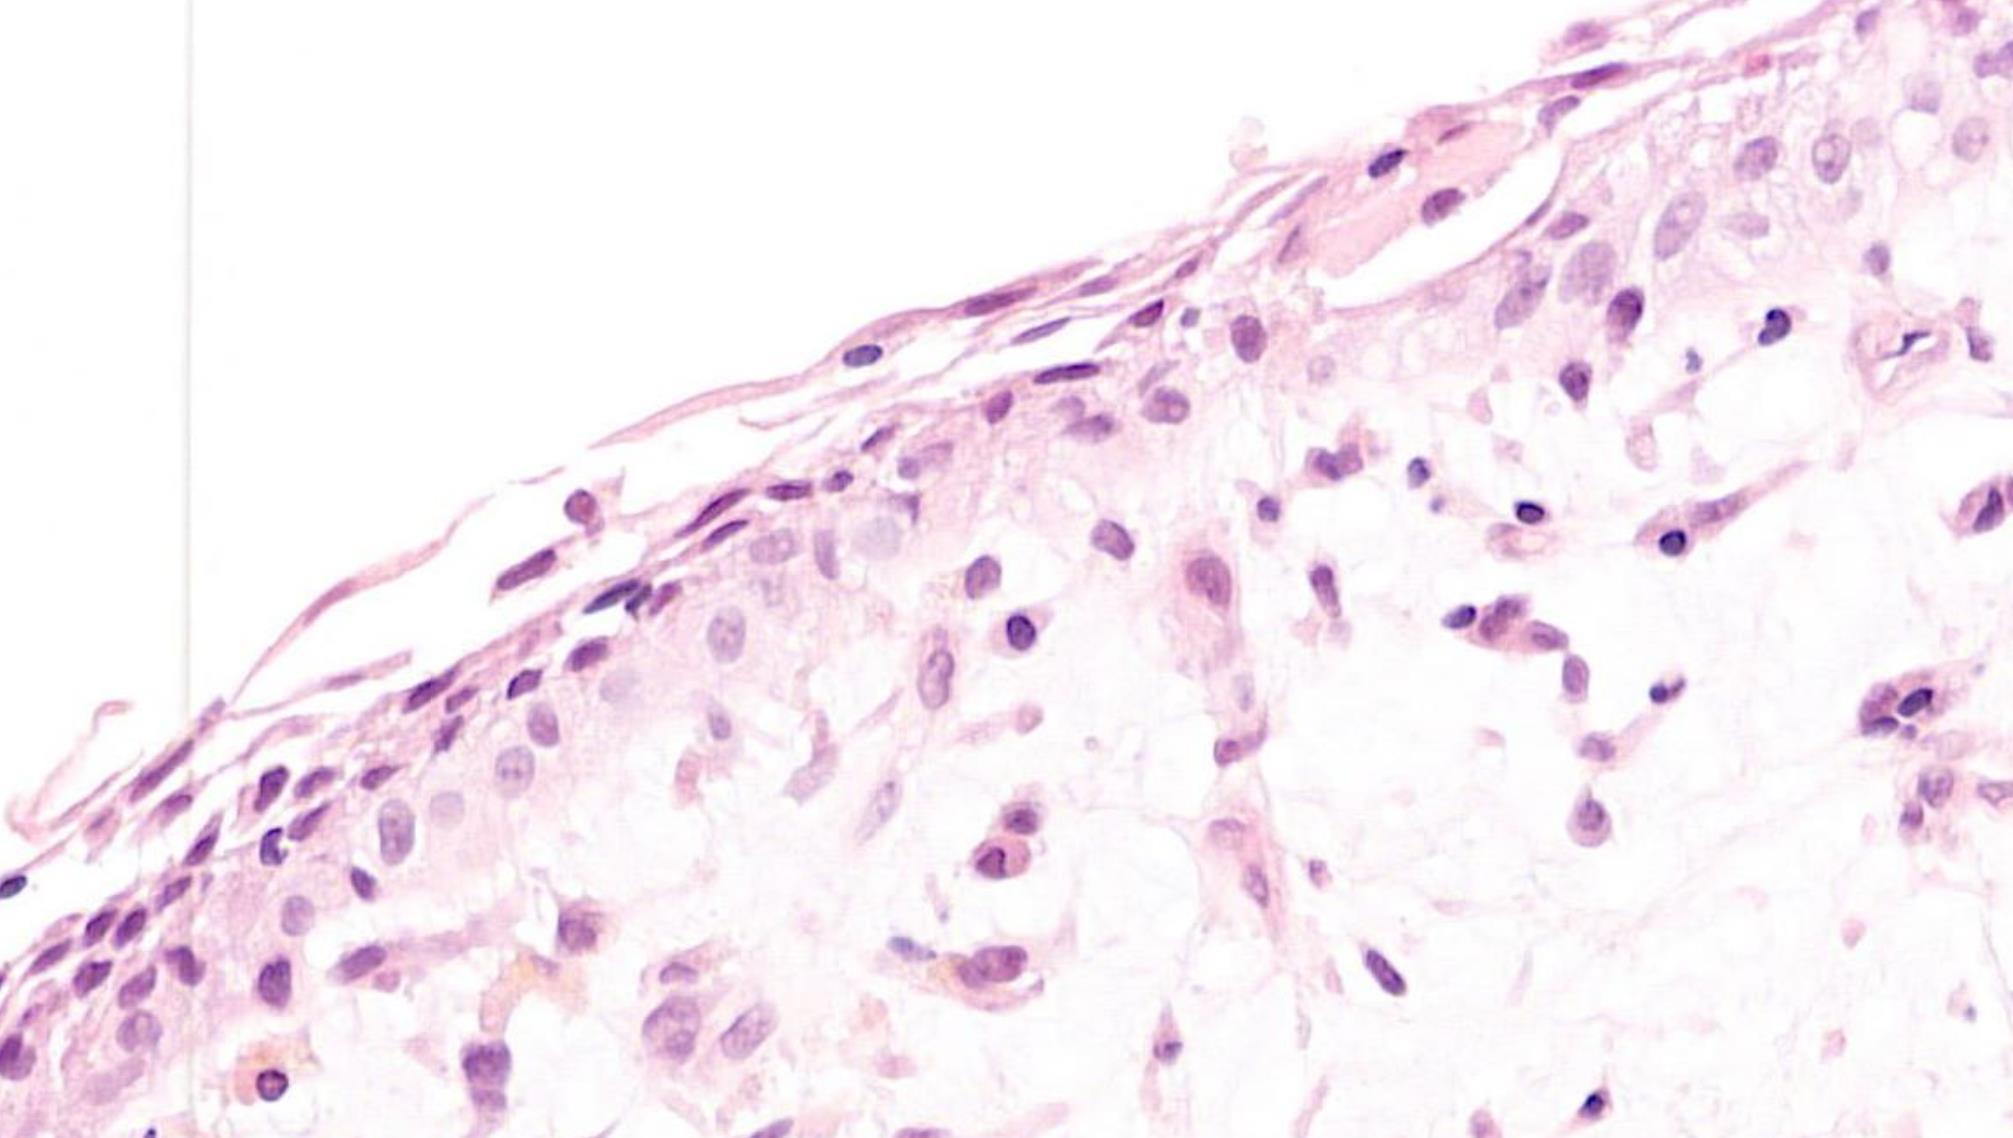

39-year-old, Male White Patch Buccal Mucosa, Smoker.

??

Case 28 Diagnosis

Lichenoid mucositis –lichen planus or lichenoid reaction